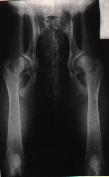

ŠPATNĚ PROVEDENÝ RTG SNÍMEK!!

Projekce není symetrická - stehenní kosti a podélná

osa těla nejsou rovnoběžné. |

Dále by se měla věnovat velká pozornost projekčně

dokonalému snímku. Jakékoli nevyhovující kvalita snímku může poté opět

negativně ovlivnit konečné hodnocení snímku, zejména v případě

hraničních stupňů dysplazie.

Na levém snímku můžeme vidět kyčelní klouby zdravého

zvířete, ale na druhém snímku je zrentgenované zvíře postižené těžkou

dysplazií.